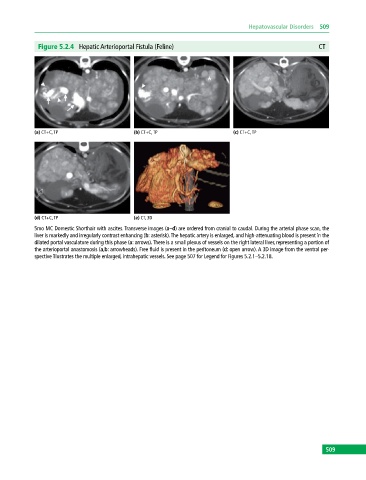

Figure 5.2.4 Hepatic Arterioportal Fistula (Feline) CT

(a) CT+C, TP (b) CT+C, TP (c) CT+C, TP

(d) CT+C, TP (e) CT, 3D

5mo MC Domestic Shorthair with ascites. Transverse images (a–d) are ordered from cranial to caudal. During the arterial phase scan, the

liver is markedly and irregularly contrast enhancing (b: asterisk). The hepatic artery is enlarged, and high‐attenuating blood is present in the

dilated portal vasculature during this phase (a: arrows). There is a small plexus of vessels on the right lateral liver, representing a portion of

the arterioportal anastomosis (a,b: arrowheads). Free fluid is present in the peritoneum (d: open arrow). A 3D image from the ventral per-

spective illustrates the multiple enlarged, intrahepatic vessels. See page 507 for Legend for Figures 5.2.1–5.2.18.